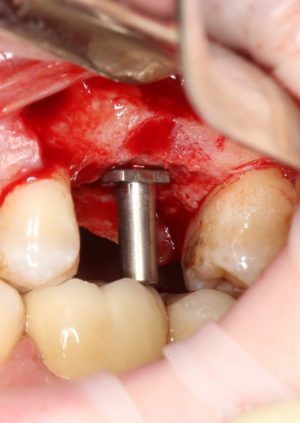

После этого можно поставить пин и проверить направление и ангуляцию оси будущего имплантата.

Кстати, о пинах. В Astra Tech они, сцуко, хитрые. Диаметр тонкого конца 2.0 мм, а толстого — 3.2 мм. Это значит, что измерить и оценить ось имплантата мы можем на этапе пилотной фрезы (2.0 мм) и следующей за ней «зеленой» (3.2 мм). Далее точные изменения становятся невозможными. Платформа-ограничитель имеет размеры 3.5 (по узкой) и 5.0 (по широкой частям) мм, что позволяет оценить положение будущей лунки относительно других имплантов и соседних зубов в окклюзионной плоскости.

После этого можно еще раз (последний, кстати), проверить направление и ангуляцию оси будущего имплантата. Всё тем же вышеозначенным пином: